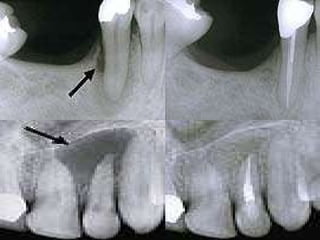

‰ ..IN FINAL STEP, A CROWN IS USUALLY PLACED OVER THE  TOOTH TO RESTORE ITS NATURAL SHINY APPERANCE. IF THE  TOOTH IS MUCH BROKEN, A POST MAY BE REQUIRED TO BE BUILD UNDER THE CROWN. ‰ ..ALL RCT PROCEDURES R DONE BY ISOLATING THE TOOTH WITH A RUBBER DAM TO PROVIDE SALIVA-FREE ENVIRONMENT. RCT MAY BE DONE IN SINGLE OR MULTIPLE VISITS DEPENDING  ON COMPLEXITY OF THE TOOTH. ‰ ..OFTEN..,X-RAYS R TAKEN TO DETERMINE THE LENGTH OF THE ROOT & TO MONITOR THE VARIOUS ASPECTS OF TREATMENT.

‰ ..IN FINALSTEP, A CROWN IS USUALLY PLACED OVER THE TOOTH TO RESTORE ITS NATURAL SHINY APPERANCE. IF THE TOOTH IS MUCH BROKEN, A POST MAY BE REQUIRED TO BE BUILD UNDER THE CROWN. ‰ ..ALL RCT PROCEDURES R DONE BY ISOLATING THE TOOTH WITH A RUBBER DAM TO PROVIDE SALIVA-FREE ENVIRONMENT. RCT MAY BE DONE IN SINGLE OR MULTIPLE VISITS DEPENDING ON COMPLEXITY OF THE TOOTH. ‰ ..OFTEN..,X-RAYS R TAKEN TO DETERMINE THE LENGTH OF THE ROOT & TO MONITOR THE VARIOUS ASPECTS OF TREATMENT.